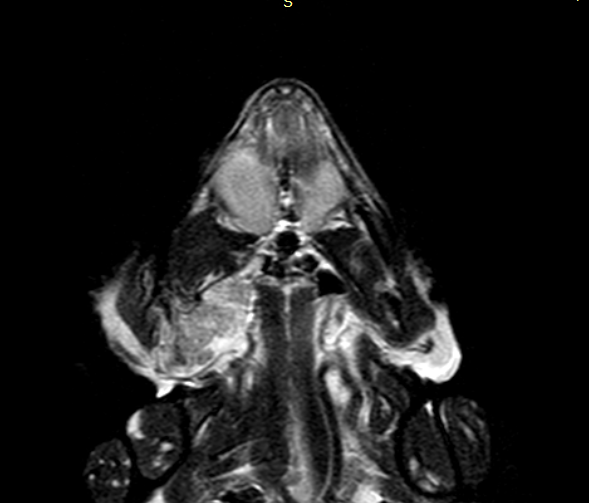

Результаты МРТ. В проекции поверхностной приводящей мышцы нижней челюсти справа, крыловидной мышцы справа, трапециевидной мышцы справа определяется объемное образование с линейными размерами 16×13×25 мм, без выраженных границ. Внутренняя сонная артерия интимно прилегает к медиальной стороне образования, которое вызывает сужение просвета ротоглотки, примыкая к правому гиоидному рожку подъязычной кости (фото 4, 5).

При внутривенном введении парамагнитного контрастного вещества – гадодиамид 0,15 ммоль/кг (омнискан 0,5 ммоль/мл, «ДжиИ Хелскеа Ирландия Лимитед», Ирландия) на отсроченных сериях определяется слабоинтенсивное накопление контраста выявленным образованием. В проекции наружной приводящей мышцы нижней челюсти справа определяется аналогичное по сигнальным характеристикам образование размером 5×4,5×3,7 мм (фото 6).